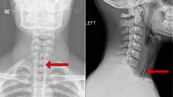

Chụp X-quang chi là chụp X-quang tại những vùng tay, cổ tay, cánh tay, bàn chân, mắt cá chân, đầu gối, hông, hoặc chân của bạn. Nó thường được thực hiện để xem liệu xương đã bị gãy hoặc bị trật khớp hay không. Vậy trong quá trình thực hiện cần lưu ý những gì? Kết quả có ý nghĩa như thế nào? Mời các bạn tham khảo bài viết dưới đây.